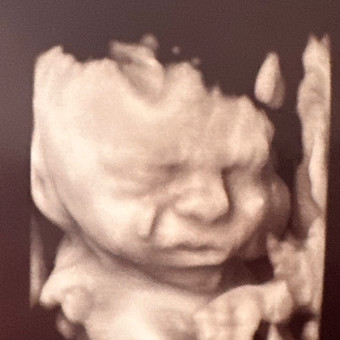

Rachel and Rodrigo’s Baby Registry

Rachel & Rodrigo Lombardo

Phoenix, AZ

March 21, 2026

Hi! Thank you for stopping by our registry! We may have gotten a little excited and purchased a good amount of newborn-3 month clothes, so if you are buying clothes, please consider bigger sizes! Hehe